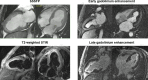

Restrictive cardiomyopathy (RCM) is a heterogeneous group of diseases characterized by restrictive left ventricular pathophysiology, i.e. a rapid rise in ventricular pressure with only small increases in filling volume due to increased myocardial stiffness. More precisely, the defining feature of RCM is the coexistence of persistent restrictive pathophysiology, diastolic dysfunction, non-dilated ventricles, and atrial dilatation, regardless of ventricular wall thickness and systolic function. Beyond this shared haemodynamic hallmark, the phenotypic spectrum of RCM is wide. The disorders manifesting as RCM may be classified according to four main disease mechanisms: (i) interstitial fibrosis and intrinsic myocardial dysfunction, (ii) infiltration of extracellular spaces, (iii) accumulation of storage material within cardiomyocytes, or (iv) endomyocardial fibrosis. Many disorders do not show restrictive pathophysiology throughout their natural history, but only at an initial stage (with an evolution towards a hypokinetic and dilated phenotype) or at a terminal stage (often progressing from a hypertrophic phenotype). Furthermore, elements of both hypertrophic and restrictive phenotypes may coexist in some patients, making the classification challenge. Restrictive pathophysiology can be demonstrated by cardiac catheterization or Doppler echocardiography. The specific conditions may usually be diagnosed based on clinical data, 12-lead electrocardiogram, echocardiography, nuclear medicine, or cardiovascular magnetic resonance, but further investigations may be needed, up to endomyocardial biopsy and genetic evaluation. The spectrum of therapies is also wide and heterogeneous, but disease-modifying treatments are available only for cardiac amyloidosis and, partially, for iron overload cardiomyopathy.